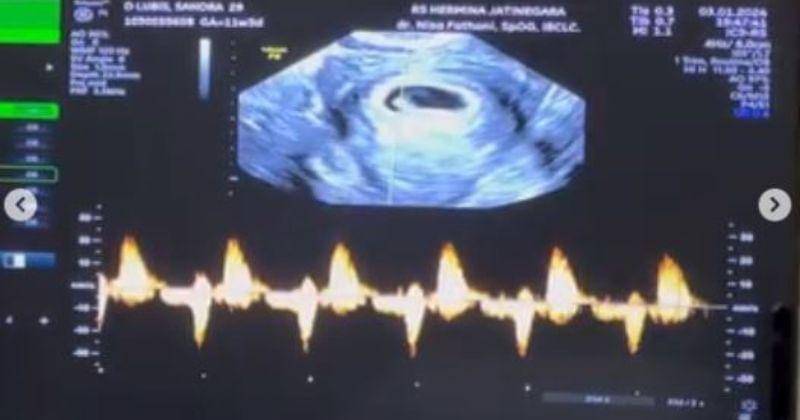

3. Detak jantung si Kecil yang didengar Sandra sampai terharu

Momen adanya janin dalam kandungan tentu menjadi anugerah besar baginya dan suami. Namun, mendengar detak jantung si Kecil secara langsung membuat Sandra haru biru.

Degupan jantung si Kecil dalam kandungannya membuat ia bahagia sekaligus emosional. Khusus untuk unggahan ini Sandra menyematkan video. Menandakan betapa spesialnya momen mendengar detak jantung pertama anaknya dalam kandungan.